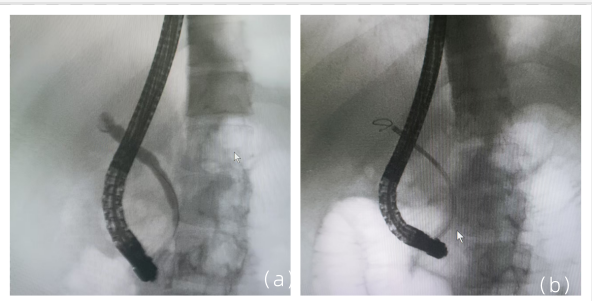

病史摘要:患者为 38 岁男性,因“发现乙肝 1 月余,腹痛 1 天”入院。1 月前诊断为“失代偿期肝硬化(脾大、腹水、门脉高压、食管静脉曲张)乙肝”,经抗 HBV、保肝治疗后症状缓解。入院前 1 天突发剑突下疼痛,进食后稍缓解,入院当日腹痛加重,伴恶心、呕吐。有吸烟及不规律饮酒史,现已戒酒,母亲因“肝硬化”去世,无慢性基础疾病、手术史、过敏史及有毒有害物质接触史。

乙肝肝硬化患者合并肝门部胆管狭窄致梗阻性黄疸罕见病因1例